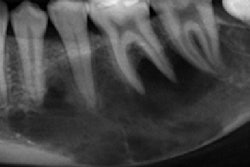

Imaging aids in removing aspirated drill head from patient

Imaging assisted in the diagnosis and removal of a dental drill head from the airway of a 76-year-old patient who aspirated the object during a procedure.

An x-ray and computed tomography scan aided in visualizing the approximately 2-cm dental drill head within the patient's right airway. Once the foreign object was retrieved, the patient recovered without incident, according to a case report published in Radiology Case Reports.